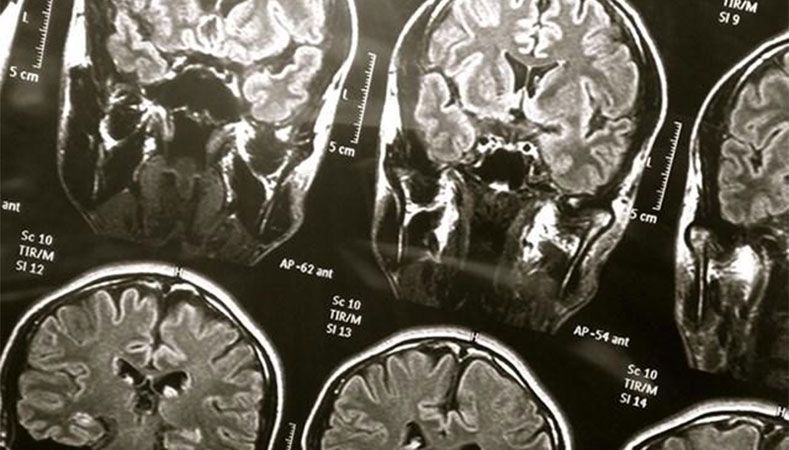

Al escanear su cerebro, los médicos detectaron una lesión de aspecto raro que hacía suponer que era de origen canceroso, por lo que se procedió a operarla.

Pero cuando los especialistas del Hospital Mount Sinai de Nueva York abrieron el cráneo de Palma el pasado septiembre, lo que vieron los dejó boquiabiertos.

En vez del tejido suave de un tumor, lo que los doctores tenían ante sus ojos era algo más parecido a una roca o un huevo de codorniz. Tras extraer el tejido y cortarlo bajo un microscopio, se dieron cuenta de que lo que estaban observando era la larva de una tenia.